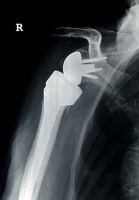

Abbildung 2: Hemiprothese, Totalprothese

Mineralstoffwechsel

Prothese

Röntgenbild

Schultergelenk